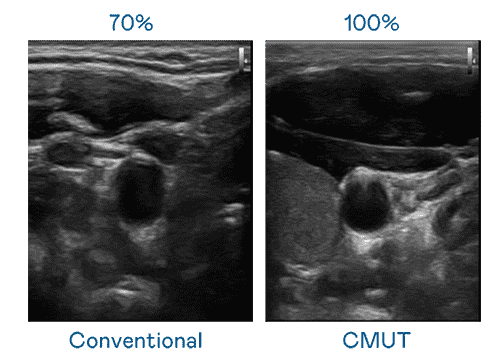

CMUT 技术是一种用电容式微机电元件来产生超音波讯号的技术。。。。与传统 PZT 压电式技术相比,,CMUT 频宽增加 30%,,更宽频的超音波讯号让影像解析度大幅提升,,,是实现高影像品质医疗超音波扫描、、、、促进精准医疗发展的关键技术。。。。

大频宽带来超清晰影像

超音波影像的解析度高低,,,首先取决于探头能发出的讯号频宽。。。z6mg·人生就是博 CMUT 可提供高清晰的超音波讯号,,,,提供高频宽、、、高灵敏度、、影像纹理细节更高的超音波影像,,,,协助医护人员缩短影像判读时间及利用精准的医疗影像进行诊断。。